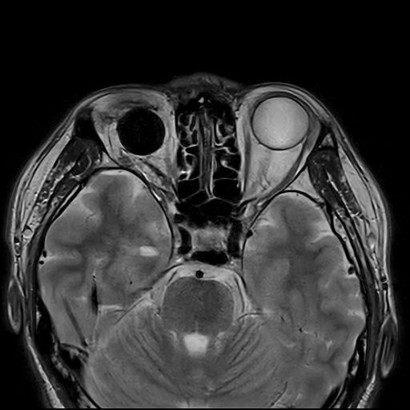

■病変がピカッと光る!『T2強調画像』

次は「T2強調画像」です。

こちらはT1とは逆で、「水が白く映る」のが最大の特徴です。

人間の体は、炎症を起こしたり腫瘍ができたりすると、そこに水分が溜まる(浮腫)性質があります。

つまり、T2強調画像では「異常な部分が白く光って見える」のです。

病気を見つけ出すための最強のサーチライトと言えるでしょう。

臨床での使いどころ:脳梗塞、炎症、浮腫、腫瘍の検出—病変の多くは水分を含むため、T2WIで白く光って見えるのが大きな強みです。